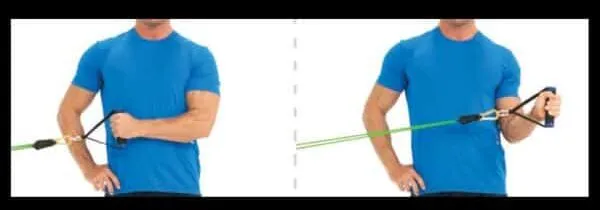

• Φυσικοθεραπεία για αποκατάσταση κινητικότητας

Μετά τη θεραπεία, ακολουθεί εξατομικευμένο πρόγραμμα φυσικοθεραπείας για αποκατάσταση του εύρους κίνησης και ενδυνάμωση του ώμου.